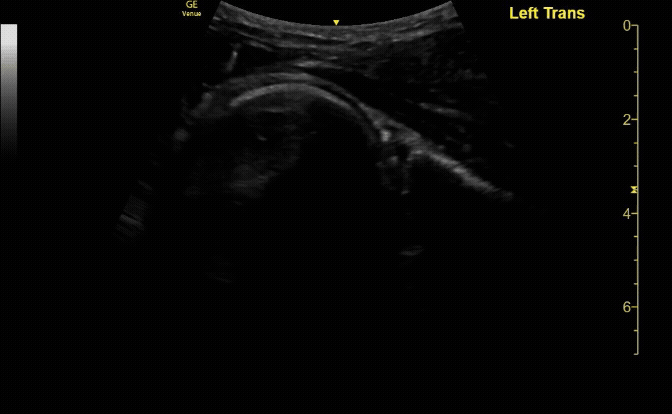

Anterior shoulder dislocation/reduction.